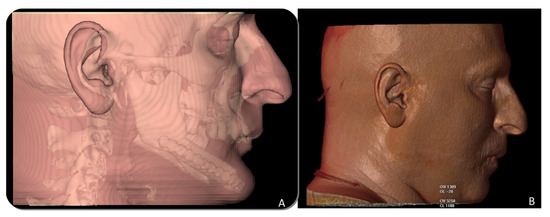

The vertical reconstruction of the fibula with the iliac crest graft doubled the original height of the fibula flap. No titanium mesh exposure was observed, and none of the grafts communicated with the oral cavity. Six months later, once the ossification of the graft was checked by panoramic radiograph and CT scan, an intraoral approach was accomplished, the titanium meshes were removed and dental implants were placed (Ticare®, Valladolid, Spain). A total of 38 implants were placed in the new mandible, with an average of 4.75 ± 0.4 implants per patient and an osseointegration success rate of 94.7%. Two implants were lost during the osseointegration period (5.3%). All patients were rehabilitated with a fixed implant prosthesis. Bone resorption was measured as peri-implant bone resorption, 3 years after prosthetic rehabilitation, through CBCT. The measurement was performed at the mesial and distal level of each implant, with a variation between 0.5 mm and 2.4 mm, and with a mean of 1.43 mm. Six patients reported a good aesthetic result while two patients described the result as fair. The morphing images showed a significant improvement in the lower facial third between the initial mandibular reconstruction and the final results after iliac crest graft, implant placement and prosthetic rehabilitation. In terms of functional results, speech articulation was evaluated as intelligible language in all patients. Seven patients reported a regular diet while one patient reported a soft diet.

CT Scan and CBCT were performed in the postoperative follow-up, and bone volume and bone resorption (Figure 13 and Figure 14) were evaluated by the Radiology Department of the hospital. A morphing reconstruction was performed to compare the lower facial third showing an improvement in the aesthetic profile and facial projection (Figure 15).

Figure 15. Aesthetic comparison. (A) Morphing performed through CT Scan after mandibular reconstruction with fibula free flap, showing a retrusion and collapse of the lower facial third. (B) Morphing performed after implant rehabilitation, demonstrating a significant aesthetic improvement after 3D reconstruction with iliac crest graft.